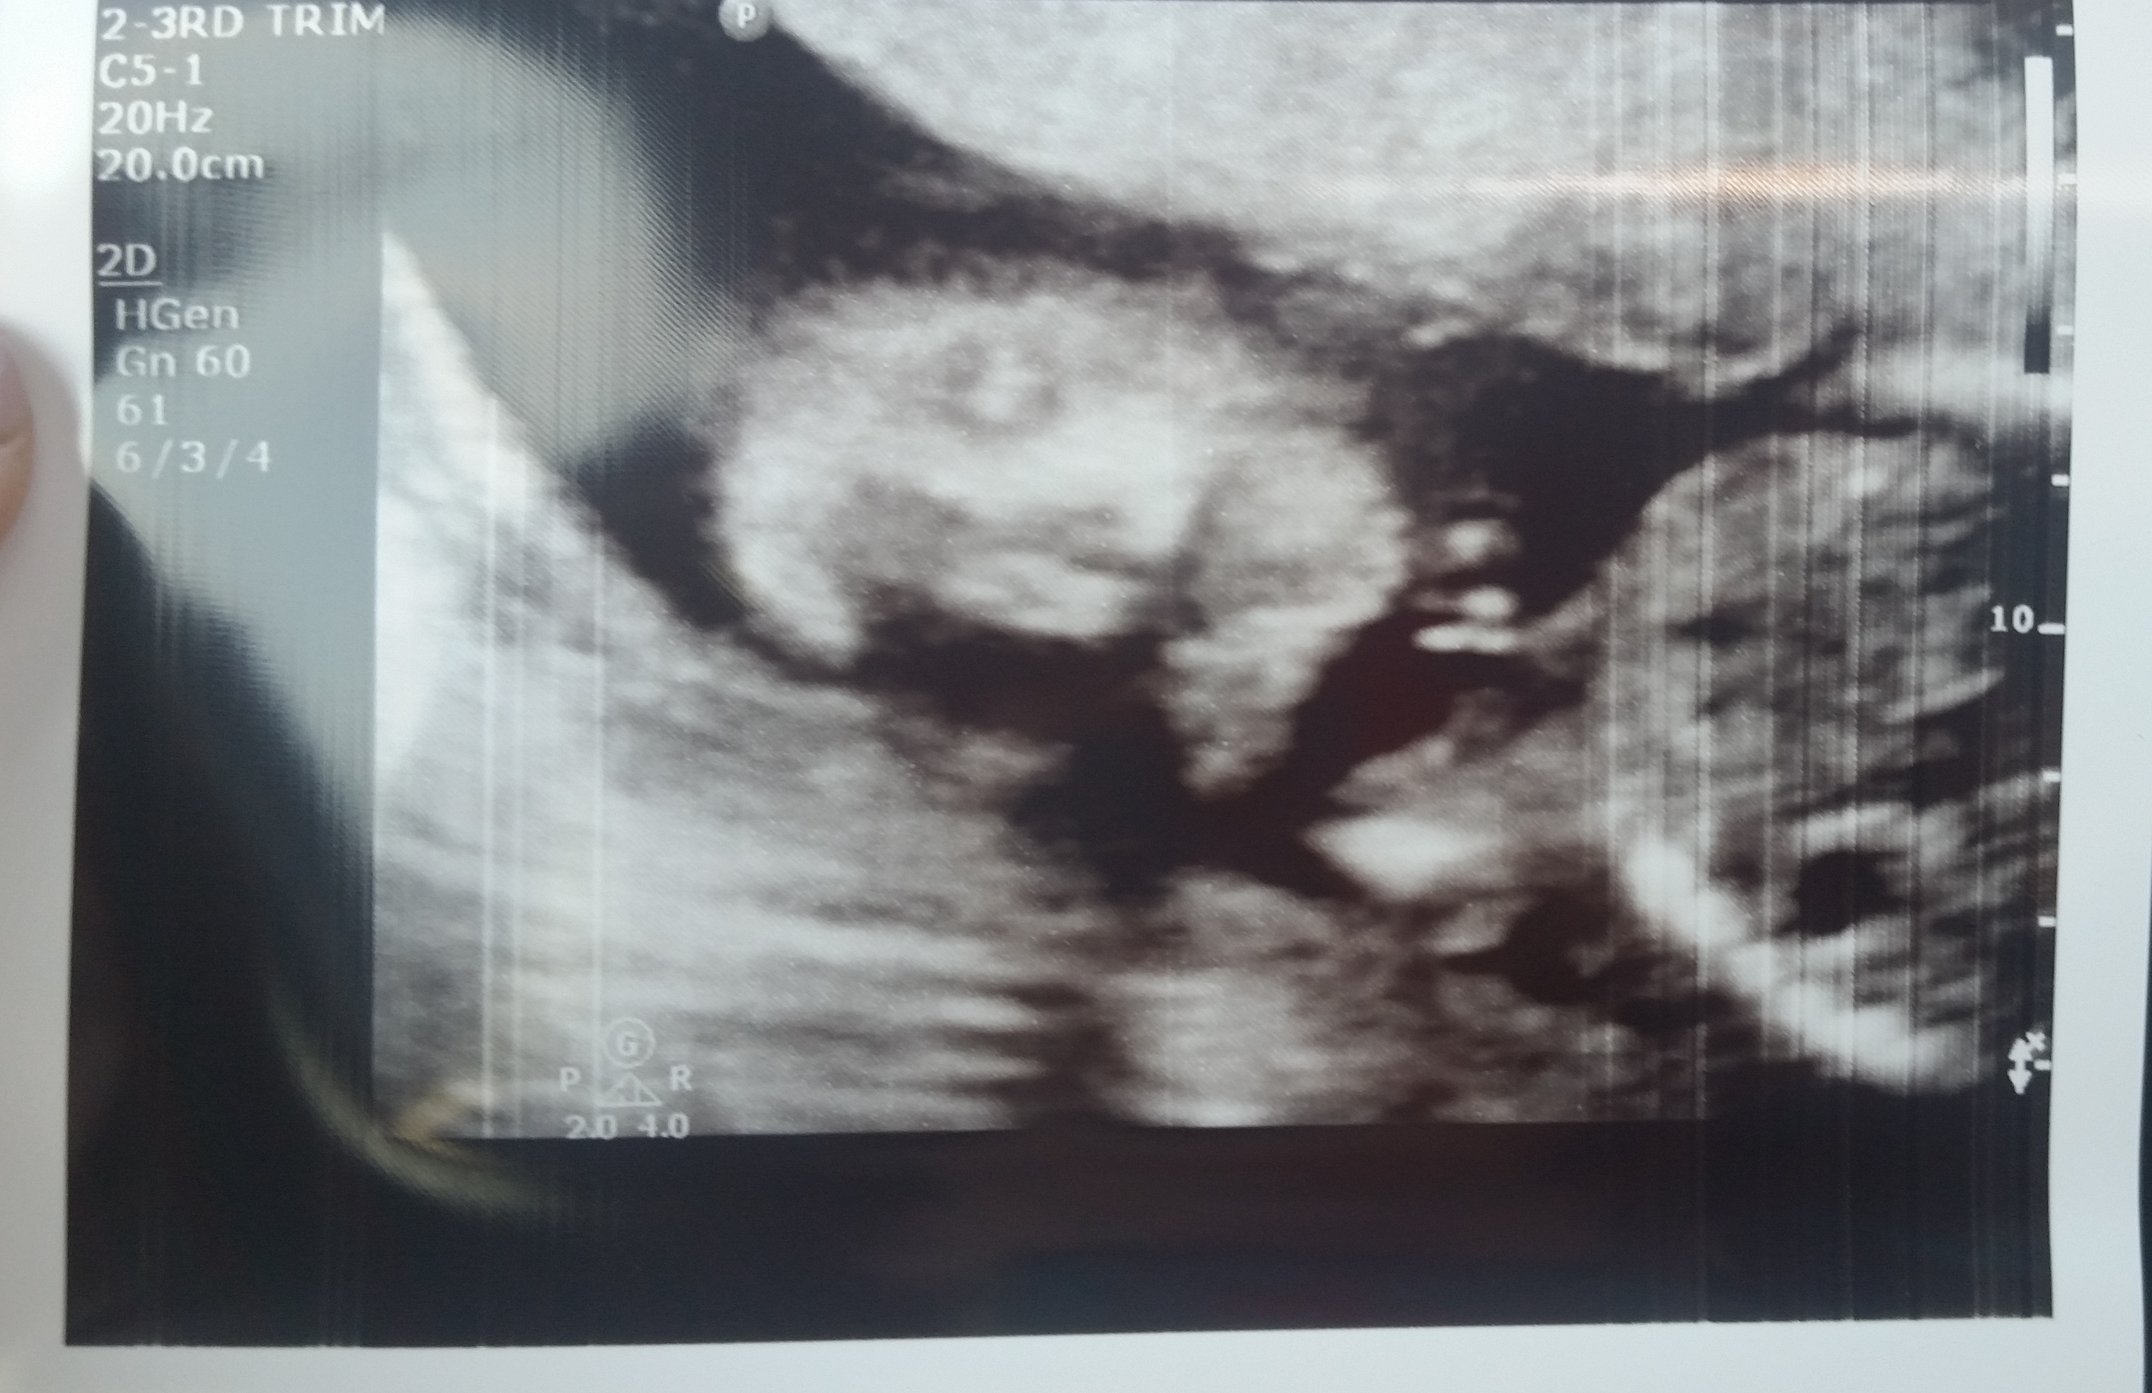

Heads of my 2 little girls! Baby A is trying to kiss baby B on the forehead. Telling her sister to catch up!! She's now 10 days behind but both are still doing good. No TTTS and hopefully will stay no TTTS. Come on babies! Grow grow my loves.

SaveSaveMarried in April 2007

One Furbaby - Adorable Pitt Mix

15 Months TTC....2nd Cycle of Letrozole - Success!

Expecting our first two little miracles - Boy/Girl Twins! - EDD March 3, 2017

High Risk Pregnancy - Type 1 Diabetic; Hypothyroidism; Di/Di Twin Pregnancy